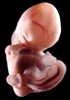

Carnegie Stage 18 (44 post-ovulatory days)

Most embryos at stage 18 are approximately 44 postovulatory days old and measure 13-17 mm in length. Distinguishing criteria for this stage include cervical and lumbar flexures, distinct notching in the hand plate, the first appearance of the elbow, eyelid folds may appear in more advanced specimens, and auricular hillocks begin to form distinct parts of the external ear.